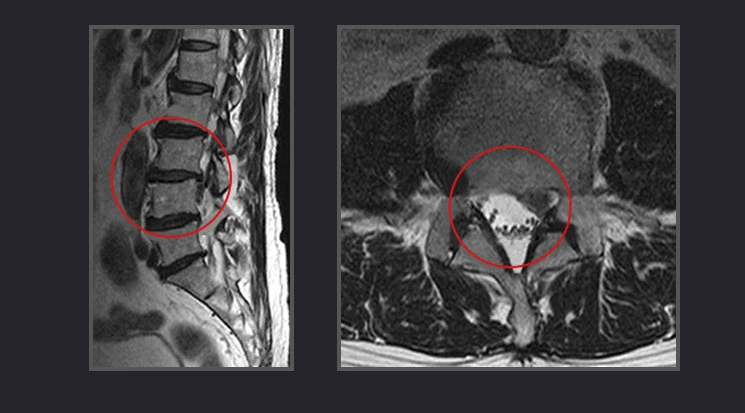

허리디스크의 정확한 질환명은 요추 추간판탈출증입니다. 척추에는 탄력성이 뛰어나 외부로부터의 물리적 충격을 완화시켜 주고 딱딱한 뼈끼리 직접 부딪히는 현상을 막아주는 디스크가 있어요. 이 디스크가 외부의 큰 충격이나 잘못된 자세 등으로 인해 디스크를 감싸고 있는 질긴 섬유륜이 손상되어 튀어나오거나 수핵이 섬유륜을 찢고 나와서 염증이 생기고 신경을 눌러 요통이나 방사통과 같은 통증을 유발하는 것이 바로 허리디스크입니다.

허리디스크1.PNG